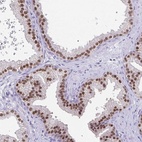

Immunohistochemical staining of human prostate shows strong nuclear positivity in glandular cells.